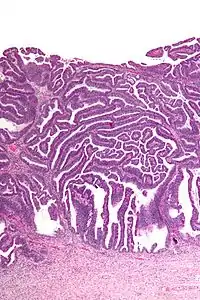

The name of the lesion describes it microscopic appearance. It has nipple-like structures with fibrovascular cores (papillae) that are long in relation to their width (villus-like), which are covered with a glandular pseudostratified columnar epithelium.

Very low mag.